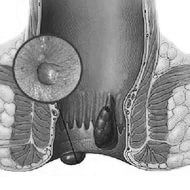

Симптоми і лікування геморою в домашніх умовах

Дані ознаки свідчать про стадії «гострий геморой», а значить необхідно робити методи комплексного лікування. Багато вважають за краще не звертатися за допомогою до фахівців і усувати проблему самостійно.

Якщо виліз геморой, що робити в домашніх умовах?

При виявленні гемороїдального вузла, потрібно швидко починати діяти, запущені випадки лікувати набагато складніше, до того ж сильний біль потрібно якомога швидше усунути.

Як лікувати зовнішній і внутрішній геморой в домашніх умовах: відмінності

Залежно від того, зовнішній або внутрішній проявився геморой, потрібно вибирати способи боротьби з ним. Природно, що для внутрішніх проявів більш ефективні свічки і мікроклізми, а для зовнішнього геморою підходять крему, мазі та гелі місцевого застосування.